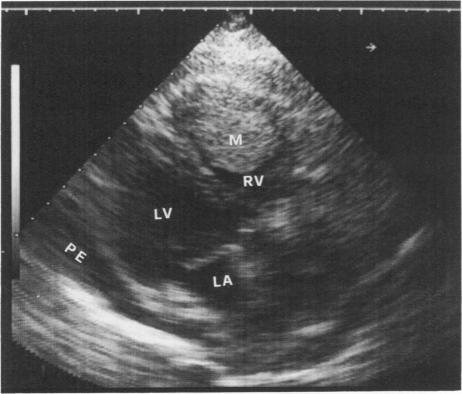

The authors report a case of cardiac metastasis of a rectal adenocarcinoma that infiltrated the right ventricle and partially obstructed its outflow tract. Surgical treatment was performed because of syncopal attacks. The differential diagnosis between organized thrombi and intracardiac tumor is considered.

作者报告了一例直肠腺癌心脏转移病例,该转移瘤浸润右心室并部分阻塞其流出道。因晕厥发作而进行了手术治疗。文中考虑了机化血栓与心脏内肿瘤的鉴别诊断。